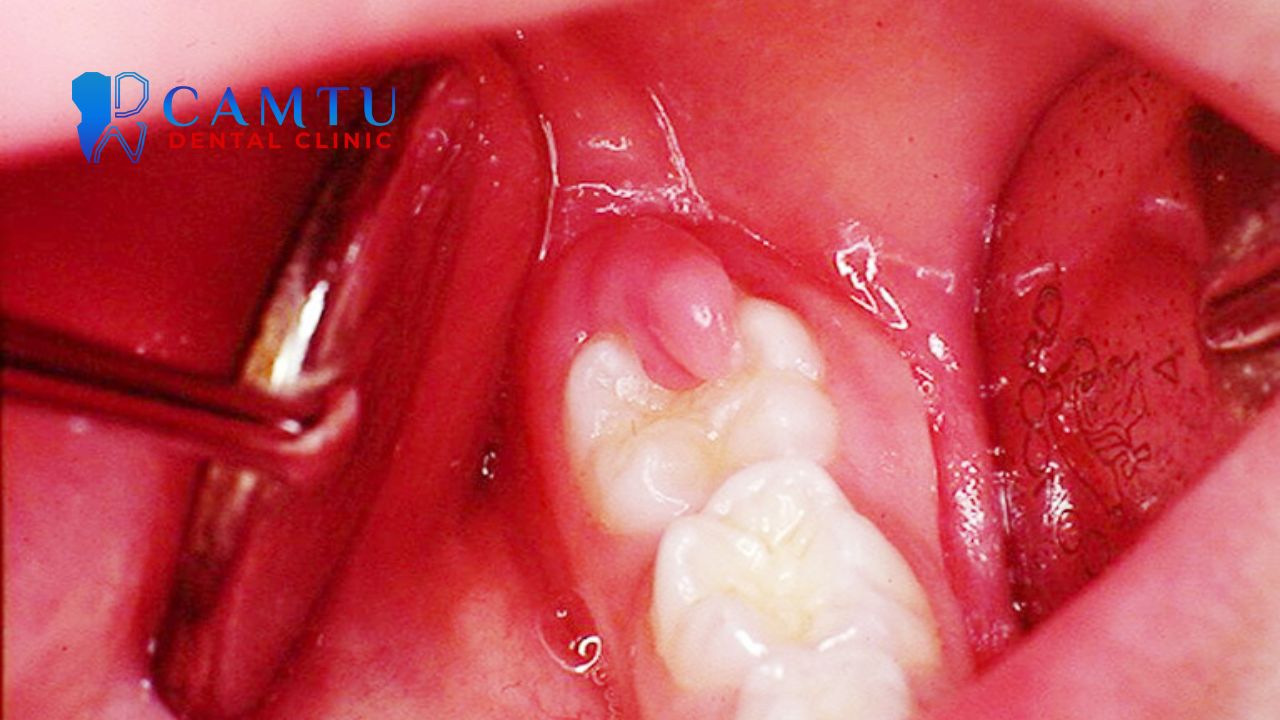

U lợi và mòn răng do ốm nghén

U lợi thai kỳ là tình trạng mô lợi tăng sinh, thường xuất hiện do sự thay đổi nội tiết khi mang thai. Khối u này đa phần lành tính, không gây đau nhưng có thể khiến lợi dễ chảy máu và gây khó chịu khi ăn nhai.

Bên cạnh đó, nôn nhiều trong giai đoạn ốm nghén có thể làm axit dạ dày bào mòn men răng. Phụ nữ mang thai nên tránh đánh răng ngay sau khi nôn, thay vào đó hãy súc miệng để trung hòa axit, giúp bảo vệ răng tốt hơn.